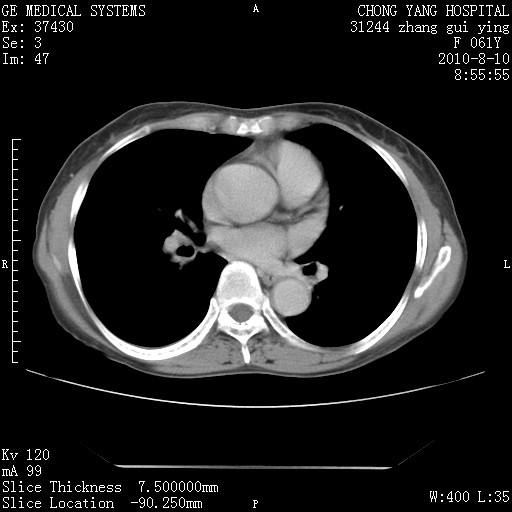

标题: CT28314:F61Y胸部增强,发热咳嗽一周入院,后面的为一周前平 [打印本页]

标题: CT28314:F61Y胸部增强,发热咳嗽一周入院,后面的为一周前平

确切的说:1:右肺下叶中心型肺癌侵及中叶支气管并中叶不张,纵膈淋巴结转移。2:左肺舌叶炎症。3:右侧胸腔少量积液

块影平扫32hu,动静脉期62-70hu.

1:右肺下叶中心型肺癌侵及中叶支气管并中叶不张,纵膈淋巴结转移。2:左肺舌叶炎症。3:右侧胸腔少量积液。支持!